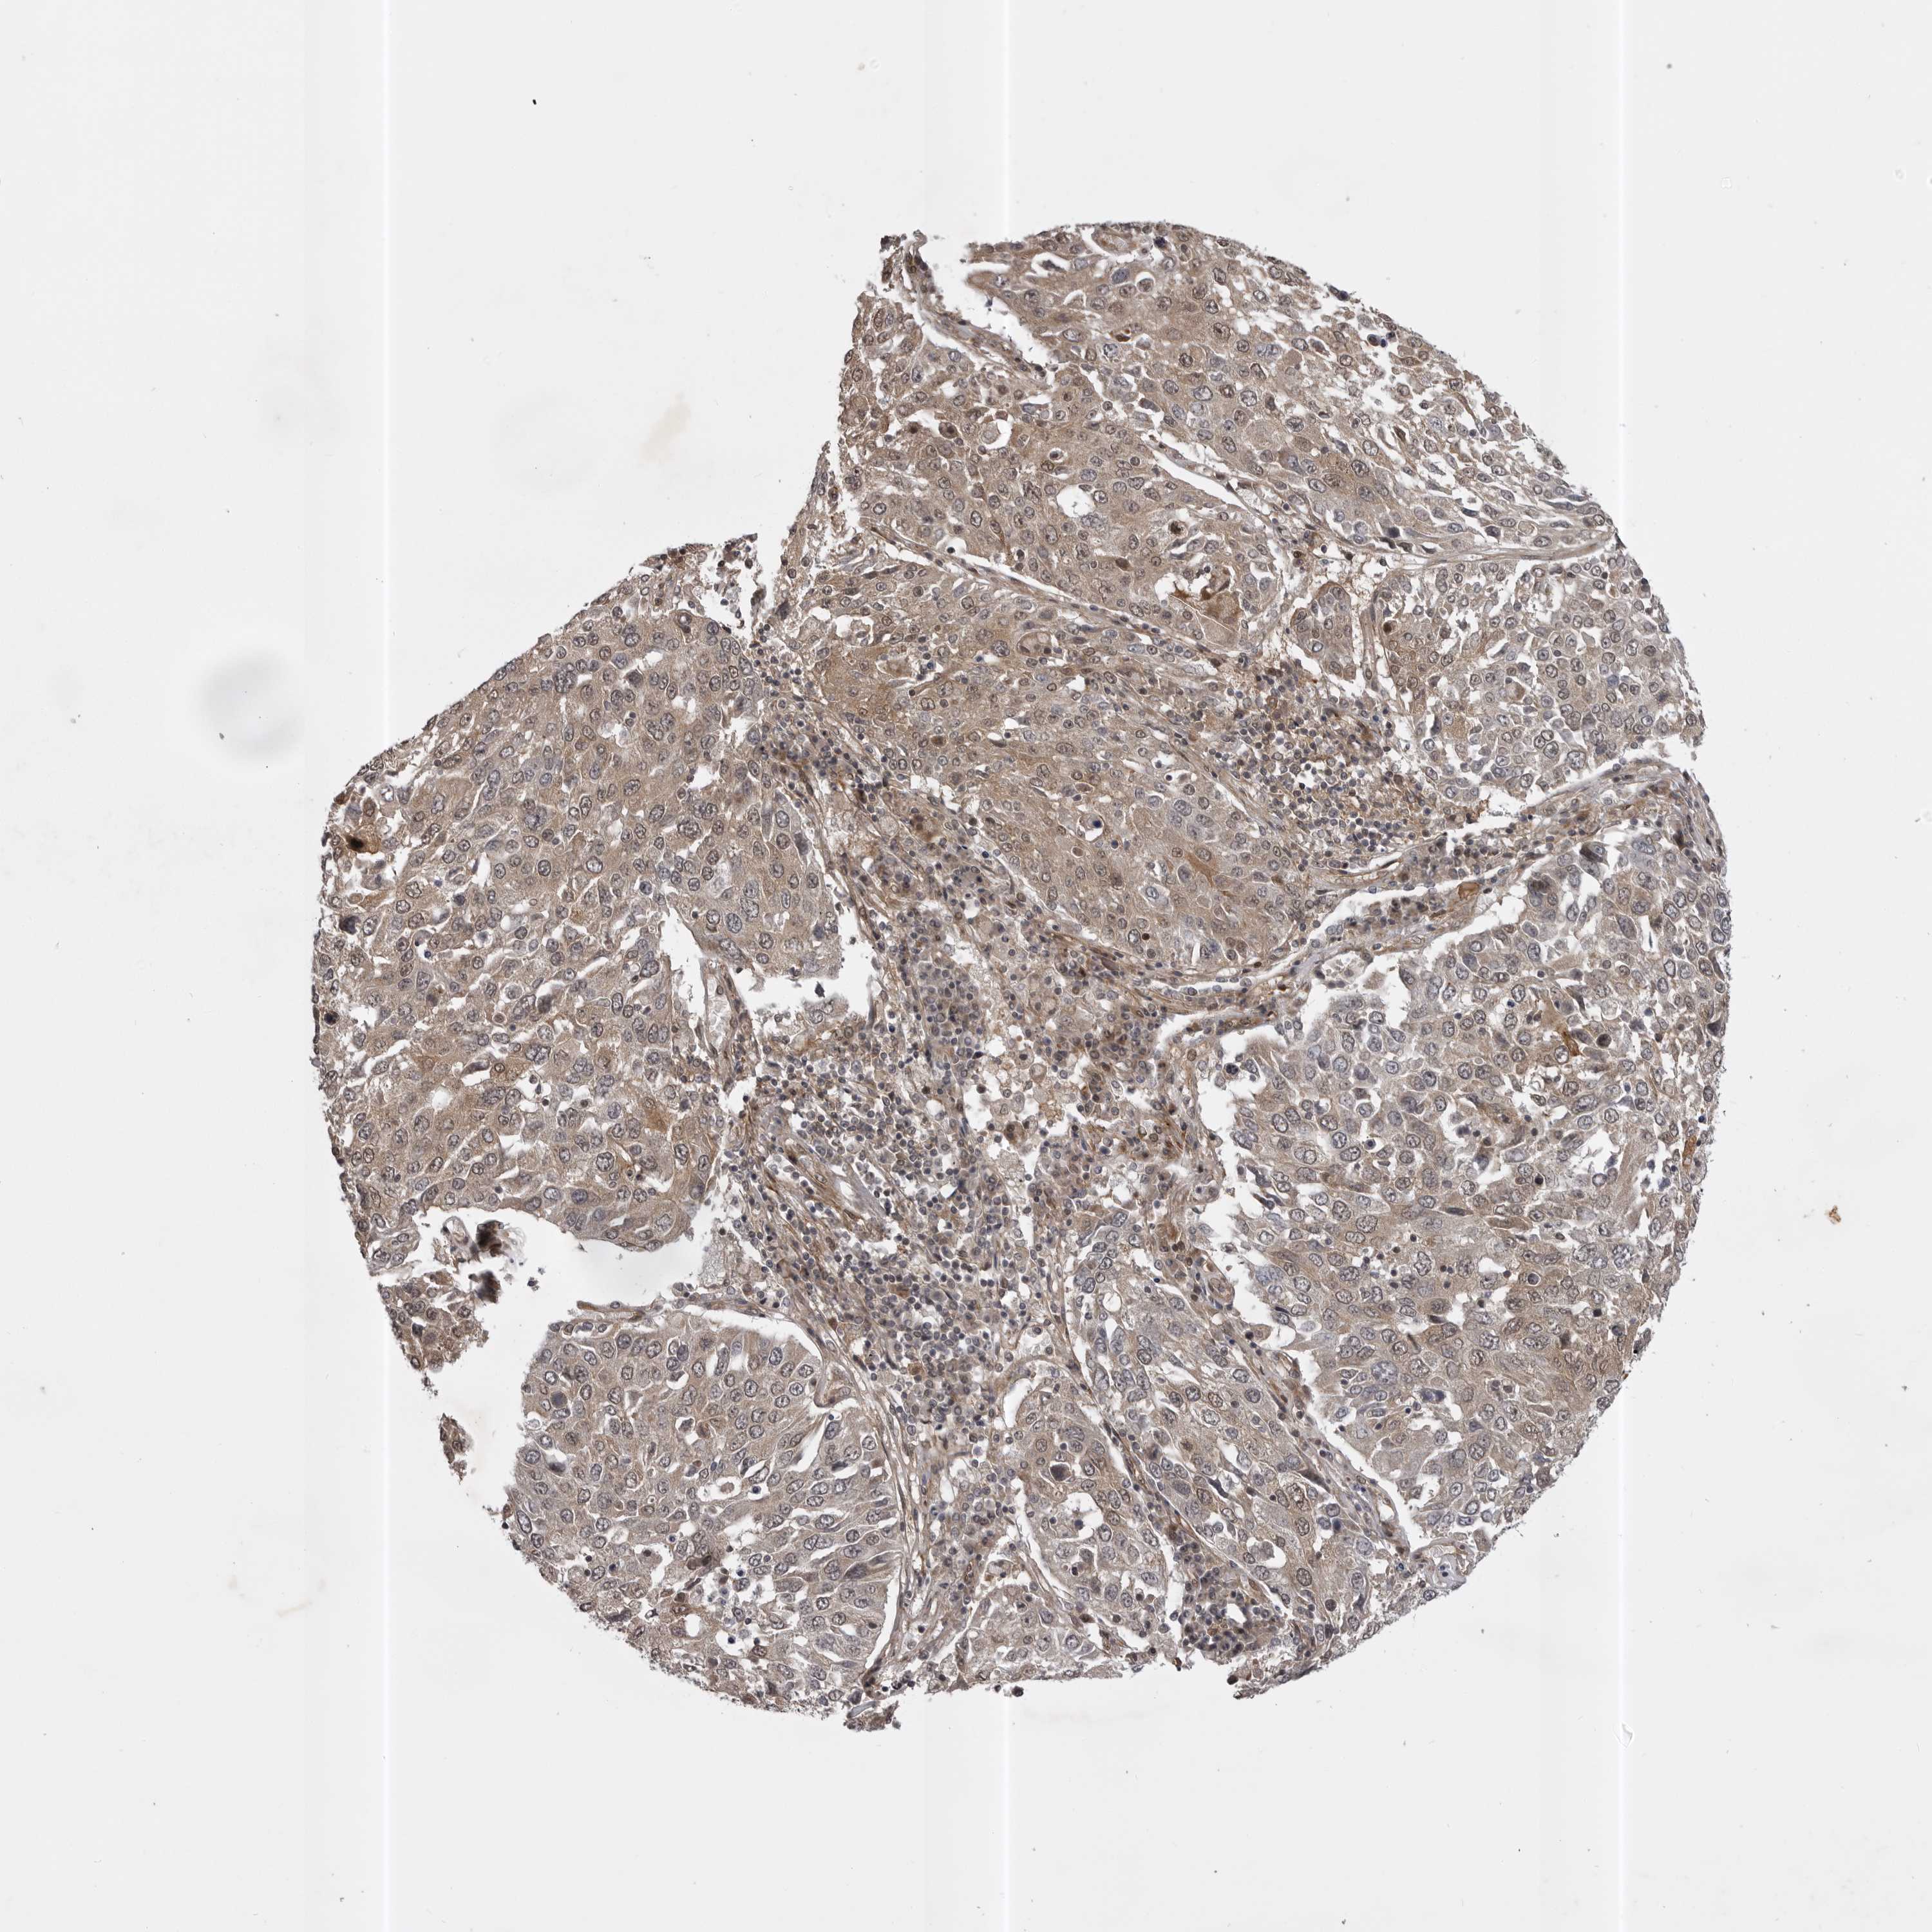

CANCER LUNG CANCER Show tissue menu

Lung cancer

Human cancer